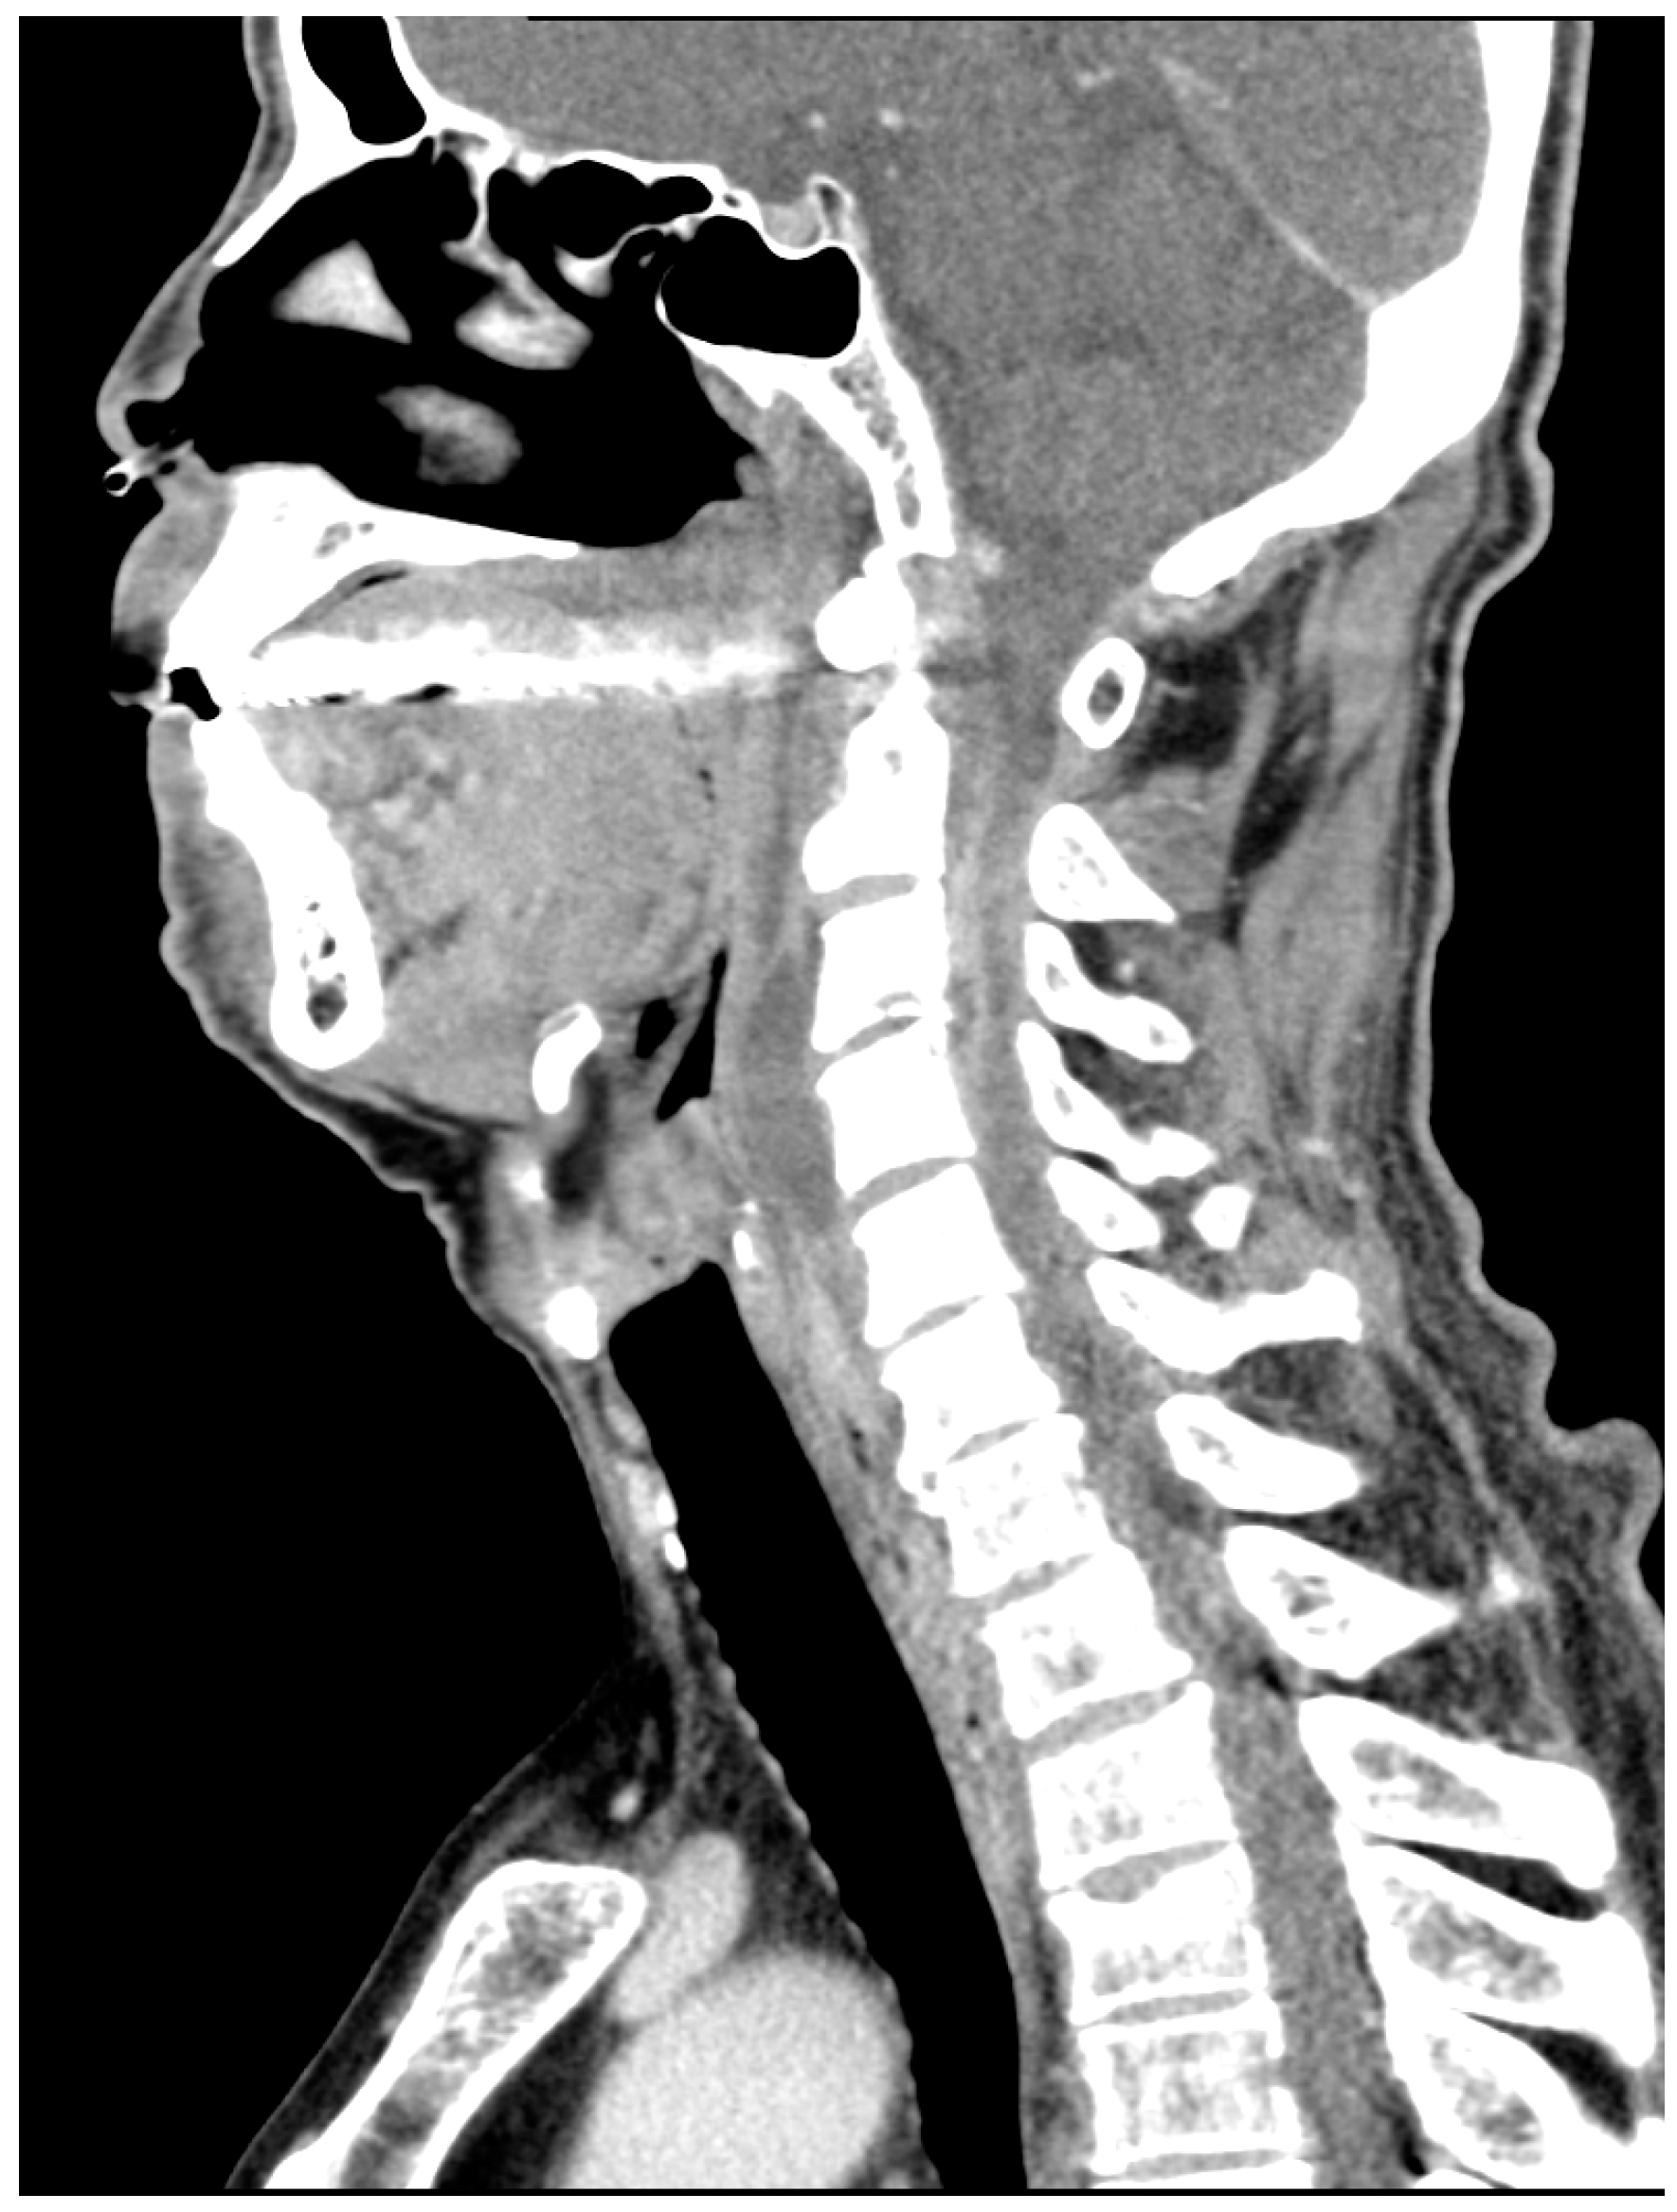

Cervical Epidural Abscess Secondary to a Post-Traumatic Hematoma, Successfully Treated with Adjunctive Hyperbaric Oxygen Therapy: A Case Report

2. Case Presentation